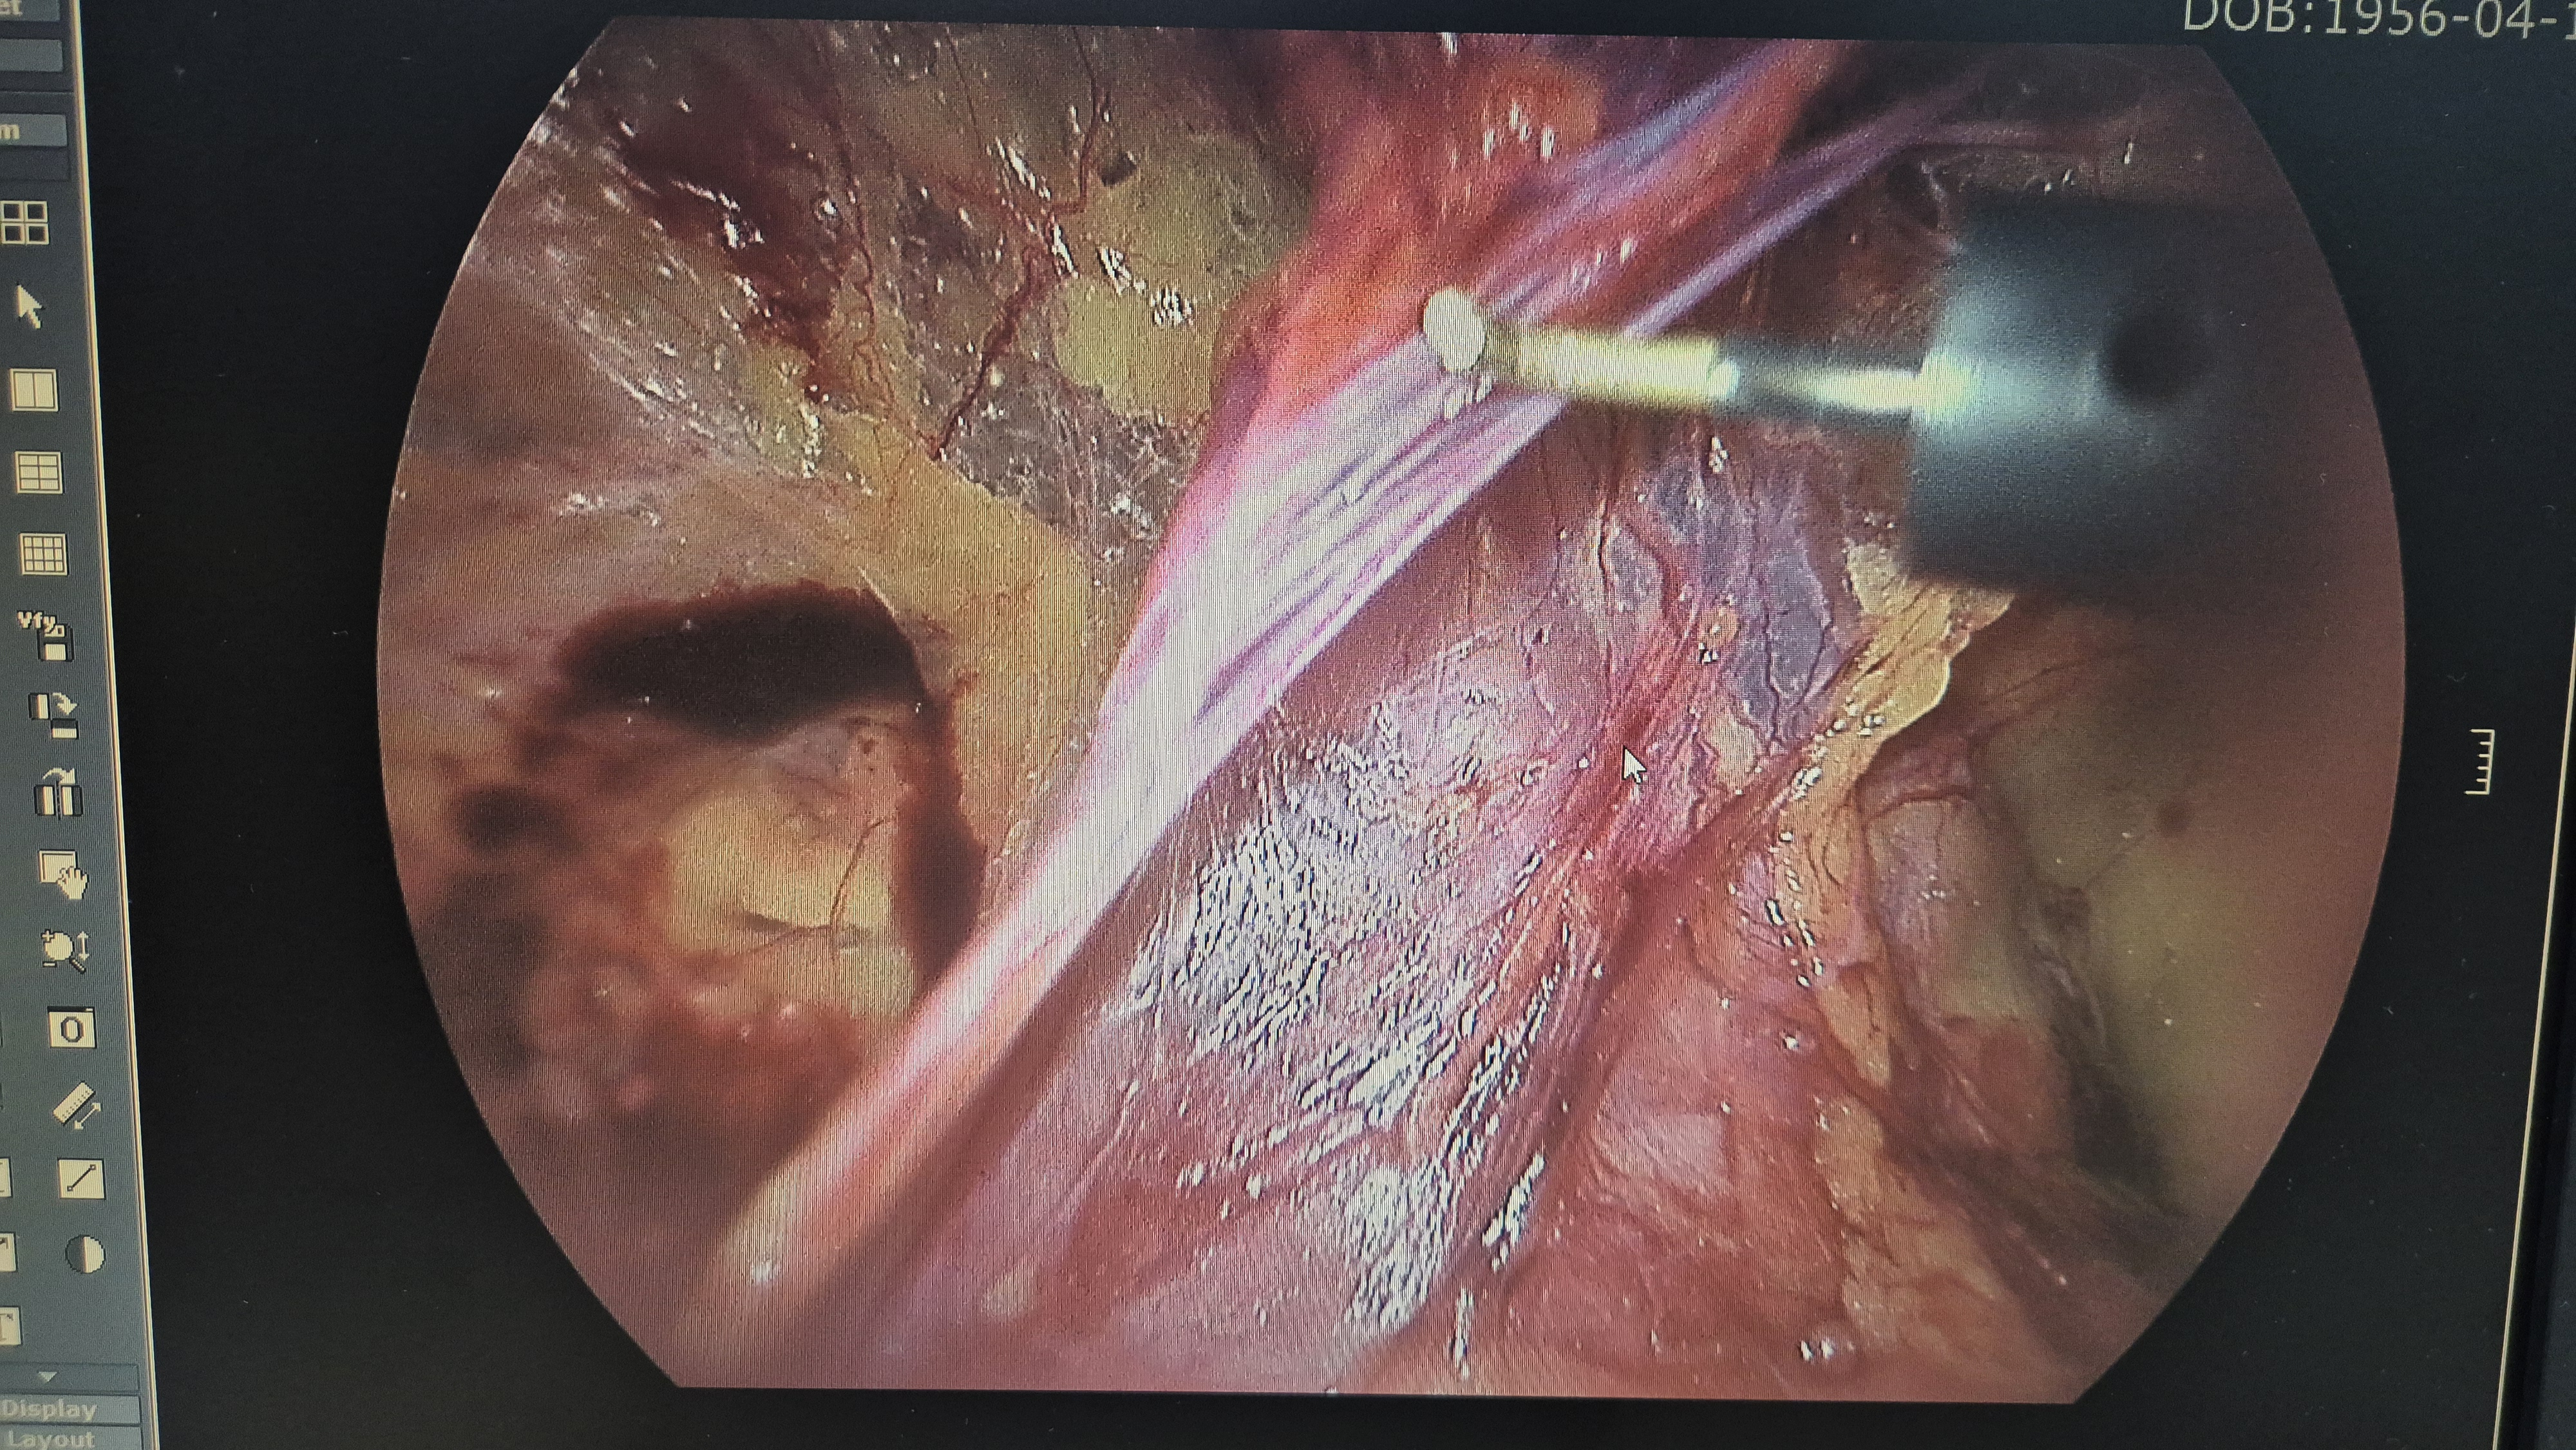

우측 서혜부 종물 주소로 내원하여 초음파 시행후 서혜부 탈장으로 확인되어,

방금 복강경 탈장교정술을 시행했습니다.

탈장 확인후.

박리.

메쉬로 고정.

수술은 15분 걸렸습니다.